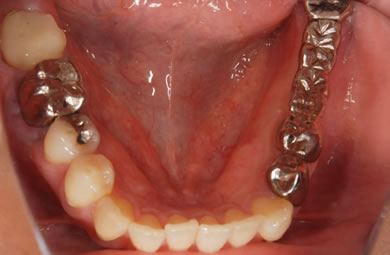

インプラントの症例写真 IMPLANT

インプラント治療+セラミック治療

| 治療方針 | 臼歯部の審美的・機能的回復をインプラント治療とセラミック治療にて行う。 | ||||||||||||||||||||||||||||||||

| 治療内容 | インプラント1本、メタルボンドセラミック2本 | ||||||||||||||||||||||||||||||||